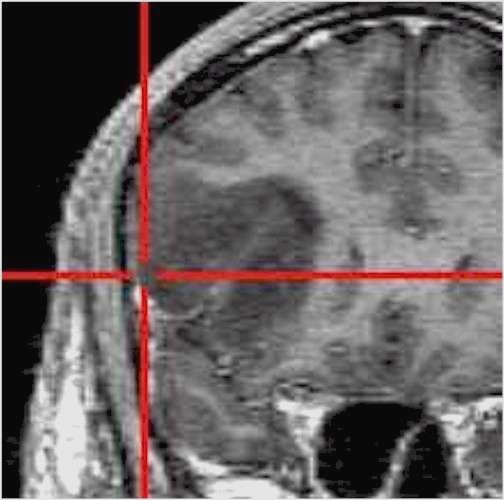

Glioblastoma

in area critica

Il procedimento ha inizio con l’esecuzione di una Risonanza Magnetica (RM) o di una Tomografia Computerizzata (TC) del paziente, effettuate mediante protocolli di acquisizione dedicati.

Al momento dell’intervento chirurgico, il capo del paziente viene registrato nello spazio tridimensionale del computer tramite un sistema di localizzazione, generalmente ottico a infrarossi, che riconosce specifici punti di repere applicati al capo o al sistema di fissaggio.

Il computer provvede quindi a sovrapporre l’anatomia reale del paziente alle immagini RM o TC precedentemente acquisite. Durante l’intervento, il chirurgo utilizza strumenti chirurgici dotati di marker che vengono continuamente rilevati dallo stesso sistema ottico a infrarossi; in questo modo il neuronavigatore è in grado di indicare in tempo reale, sulle immagini RM o TC, l’esatta posizione degli strumenti all’interno del campo operatorio.

Grazie a questa tecnologia, l’intervento viene accuratamente pianificato alla consolle del computer, anche nei giorni precedenti l’atto chirurgico, consentendo di valutare in modo approfondito il percorso di accesso più sicuro e riducendo significativamente il rischio di dover effettuare scelte intraoperatorie non sufficientemente ponderate.

Per raggiungere una determinata sede, anche se profonda o localizzata in aree critiche, è possibile adottare traiettorie talvolta più lunghe ma che attraversano regioni cerebrali a minore rischio funzionale per il paziente. In questo modo sono venuti meno molti dei limiti legati alla difficoltà di accesso anatomico (lesioni profonde, sedi eloquenti), che in passato spesso precludevano un trattamento chirurgico.

Oggi, il principale limite all’intervento chirurgico non è più di tipo tecnico, bensì biologico, rappresentato da un’estesa infiltrazione tumorale che ne impedisce un’asportazione radicale e sicura. |